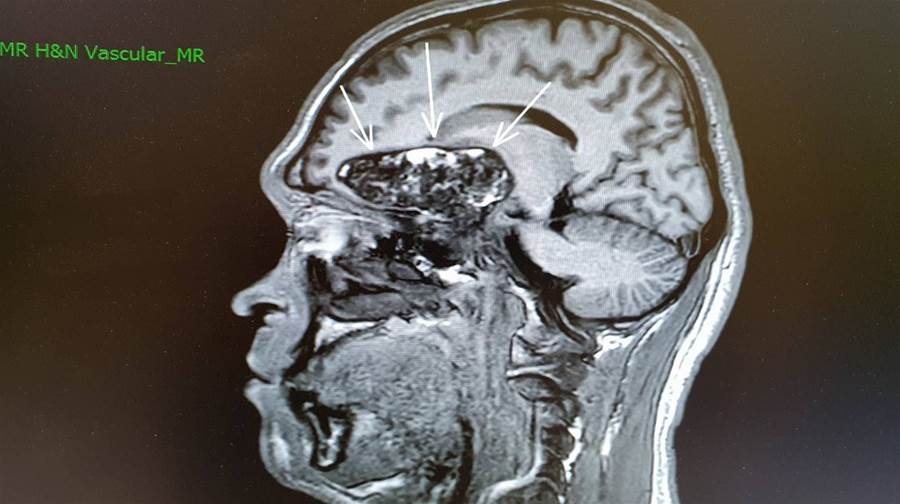

張開屏說,經過腦部核磁共振掃描後,發現腦部的松果體部位發現直徑約1.75公分的生殖細胞瘤,壓迫大腦導水管,導致腦室脊髓液無法順暢流出,因而產生阻塞性水腦,進而使腦壓過高才會劇烈頭痛。